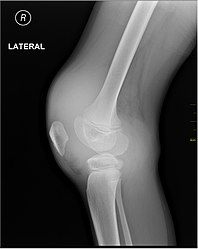

Joint capsule

Muscle and joint haemorrhages – or haemarthrosis – are indicative of haemophilia,[7] while digestive tract and cerebral haemorrhages are also germane to other coagulation disorders.

Repeated bleeds into a joint capsule can cause permanent joint damage and disfigurement resulting in chronic arthritis and disability. Joint damage is not a result of blood in the capsule but rather the healing process. When blood in the joint is broken down by enzymes in the body, the bone in that area is also degraded, this exerts a lot of pain upon the person afflicted with the disease.[8][9][10]